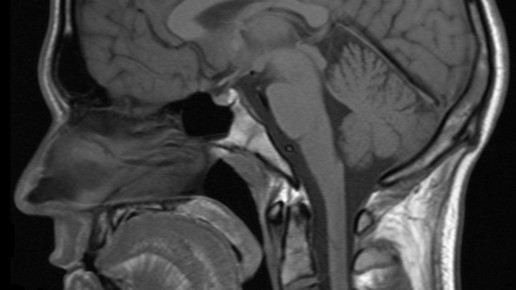

„Es war, als würde mein Körper innerlich verbrennen“, erzählt O‘Kelley in einem Bericht, den das ARD-Magazin „plusminus“ aufgreift und dem Thema eine ausführliche Sendung widmet. „Ich sah den Tod in ihren Augen“, sagt Ehemann Chuck Norris, „mir wurde bewusst, dass ich etwas tun muss.“ Sie bekam hintereinander drei Untersuchungen im Magnetresonanz-Tomographen. Jedes Mal wurde ihr dabei ein Kontrastmittel mit Gadolinium gespritzt. Das ist ein Metall, das zu den Seltenen Erden zählt und giftig ist. Monatelang litt sie unter Muskelschwäche, Atemproblemen und unerträglichen Schmerzen.

In Reinform ist das Schwermetall hochgiftig. Um es als Kontrastmittel verwenden zu können, wird es in einen molekularen Käfig verpackt und erst dann gespritzt. Das Kontrastmittel macht Gefäße und Tumore besser sichtbar. Bislang ging man davon aus, dass es sich im Urin wieder schnell abbaut.

Eine trügerische Sicherheit. Dr. Susanne Wagner, eine Wissenschaftlerin, die sich seit den 90er-Jahren mit Kontrastmitteln beschäftigt, sagt: „Schon zur damaligen Zeit war bekannt, dass bestimmte Mengen des Kontrastmittels im Körper bleiben. Sie lagern sich in Organen, Knochen und der Haut ein. Das ist auch so in den Zulassungsreports beschrieben.“ Als es zu Todesfällen kam, die damit in Verbindung gebracht wurden, wurde Aluminium für Nierenkranke verboten. 2014 wurde eine japanische Studie veröffentlicht, die belegte, dass sich Aluminium auch im Körper gesunder Menschen ablagern kann, vor allem im Gehirn.